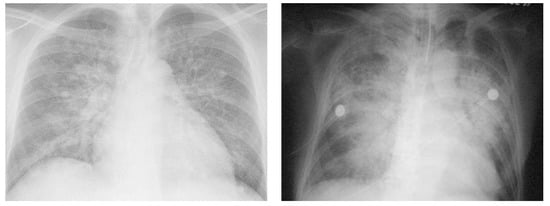

- Gluecker, T.; Capasso, P.; Schnyder, P.; Gudinchet, F.; Schaller, M.D.; Revelly, J.P.; Chiolero, R.; Vock, P.; Wicky, S. Clinical and radiologic features of pulmonary edema. Radiographics 1999, 19, 1507–1531, discussion 1532–1533. [Google Scholar] [CrossRef]